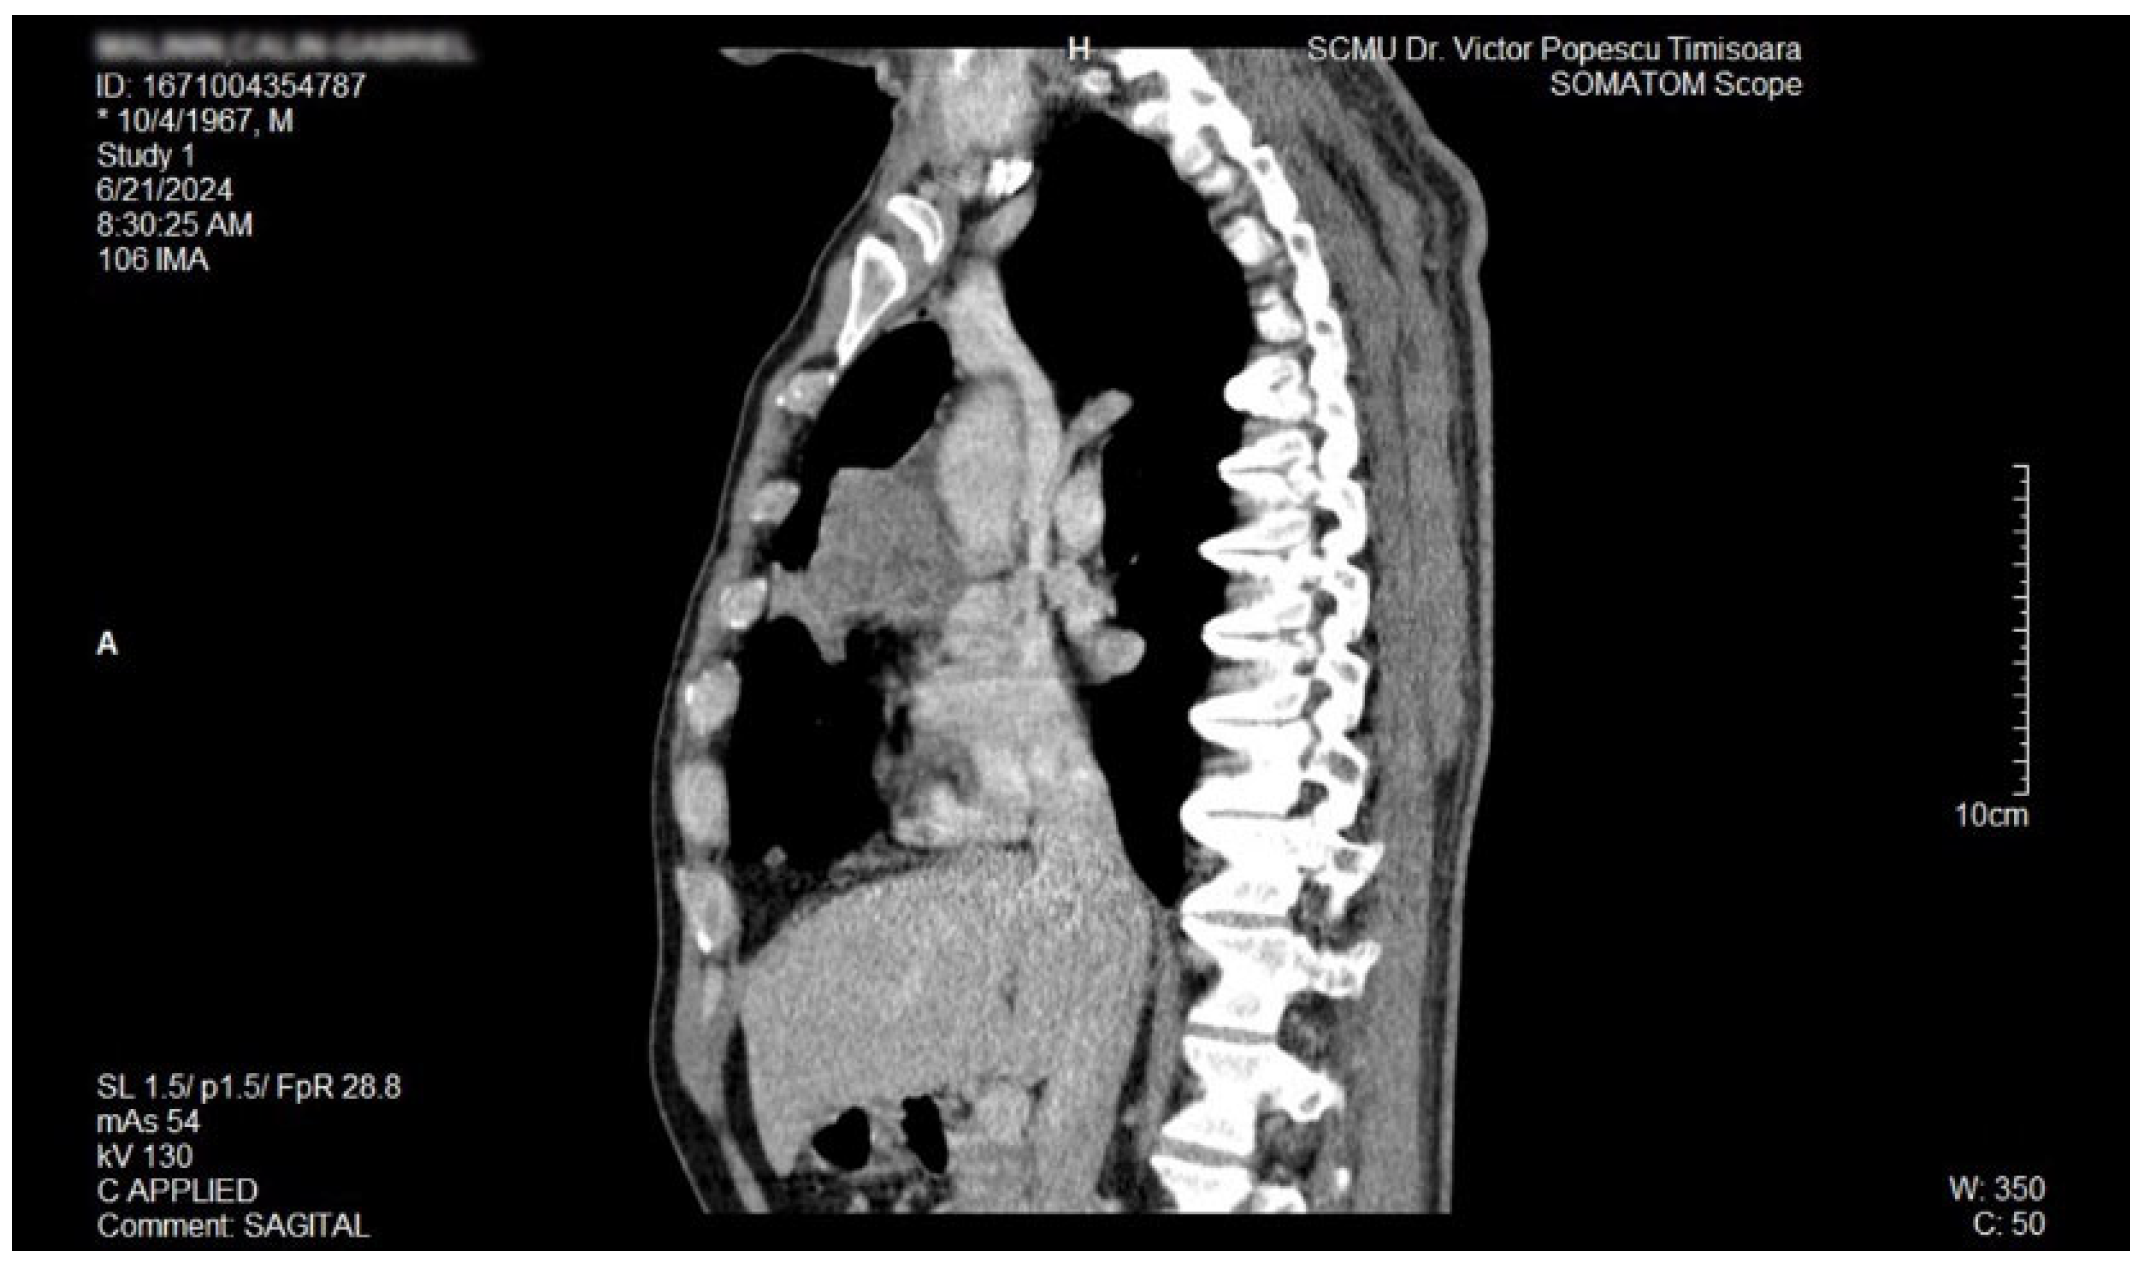

2. Case Report